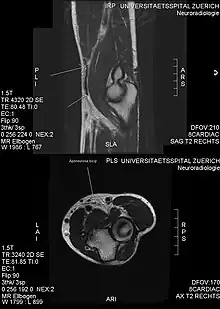

Another injury caused by bicep curls is ulnar neuropathy, which lead to ulnar nerve conduction slowing at the elbow. This is caused by compression of the nerves against a weight bench during the exercise.[23] Though unlikely, bicep curl can cause a rupture of the pectoralis major muscle, which is a severe injury that occurs in the chest.[24]